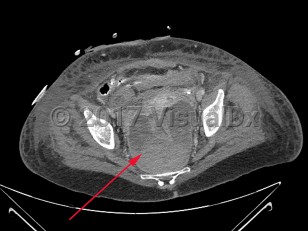

Perirectal abscess

A perirectal abscess is a collection of pus in the perianal area resulting from progression of an infected anal gland.

The diagnosis is made based on the history and a compatible physical examination. Imaging studies, including computed tomography imaging, may also be helpful.